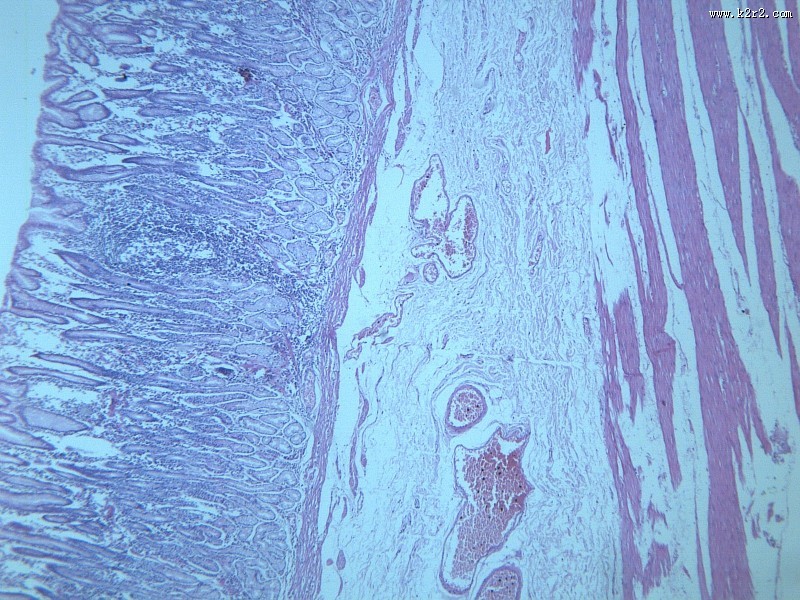

慢性萎缩性胃炎大全 - 第8张

第 8 / 12 张

慢性萎缩性胃炎大全

图集中 / 共有 12 张图片

显微切片

chronic atrophic gastritis

慢性萎缩性胃炎

消化道疾病